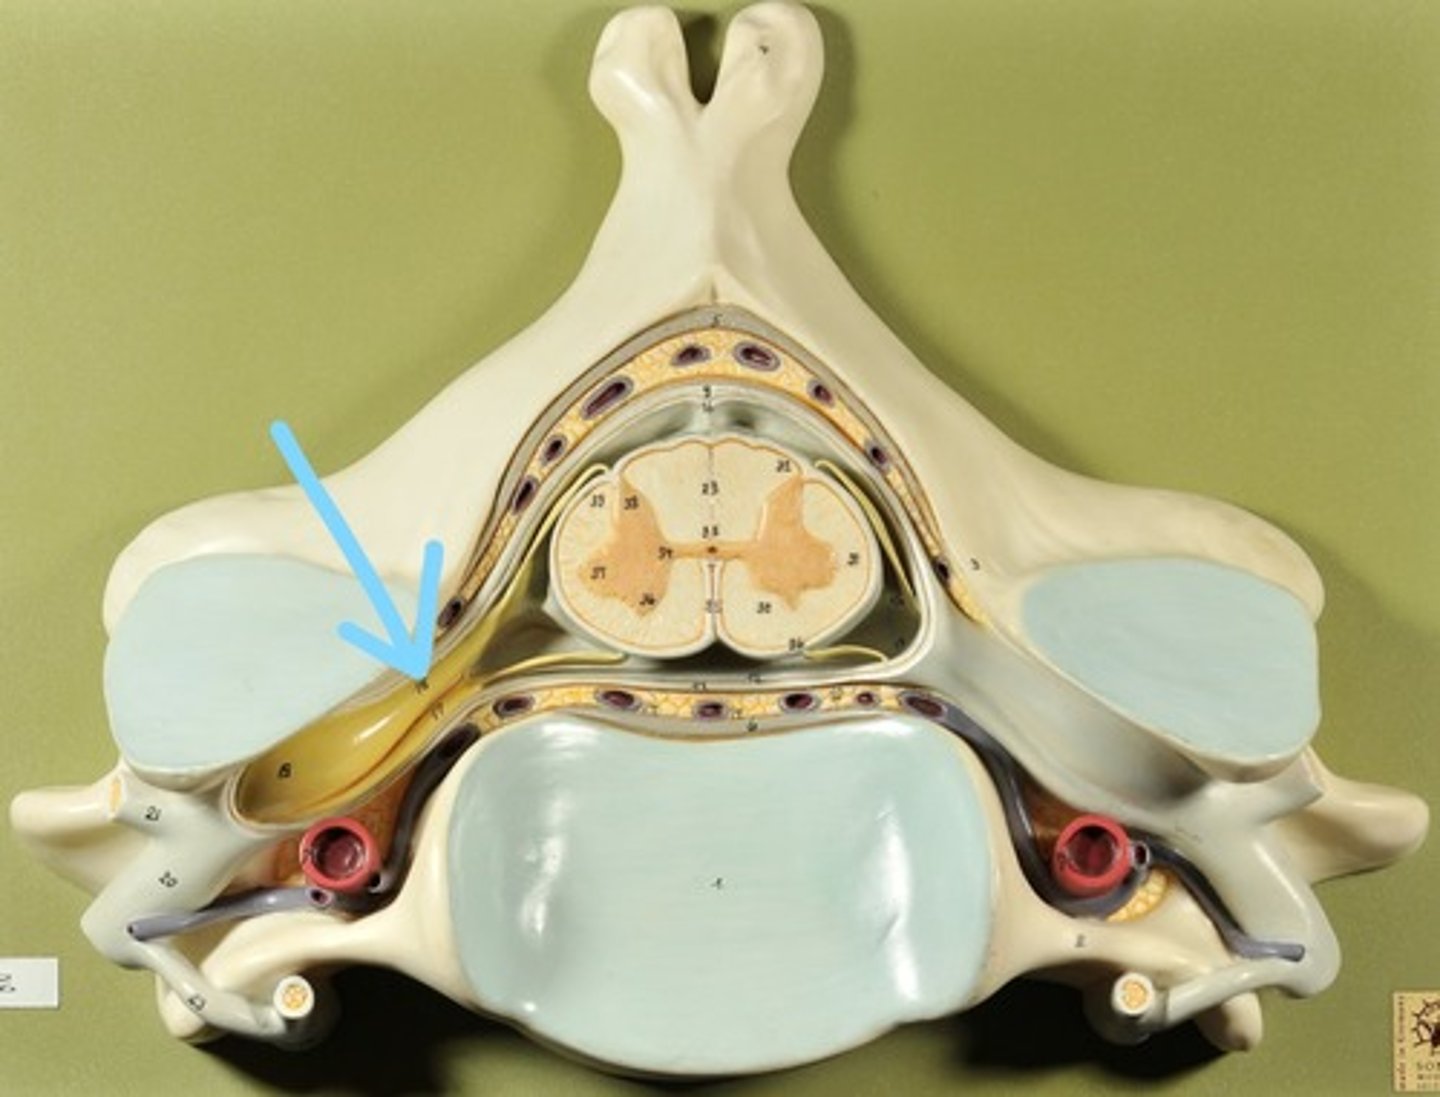

Identify all structures of spinal cord

White Matter of spinal cord

gray matter of spinal cord

Ventral Horns (gray matter)

Lateral Horns (gray matter)

Dorsal horns (gray matter)

Anterior Columns (white matter)

Lateral Columns (white matter)

Posterior Column (white matter)

central canal of spinal cord

Identify all structures

Pia Mater

Subarachnoid Space

Arachnoid mater

Subdural Space (brown line)

Dura mater

Epidural Space

Dorsal Root Ganglion

Dorsal Root

Ventral Root

Spinal Nerve